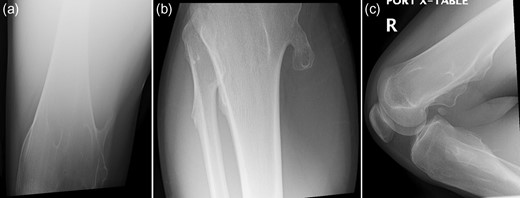

The patient is an 18-year-old female with history of MHE with many osteochondromas throughout her lower extremities who presented with acute right medial knee pain and inability to extend her knee, locked in a flexed position. The patient reports squatting in deep flexion when she felt a pop on the medial aspect of her right knee resulting in an acute inability to actively, passively or forcefully extend her knee past 90° of flexion. She has a remote history of fracture involving a right medial proximal tibial osteochondroma that has since healed uneventfully. On examination, there was tenderness localized to the medial hamstrings and soft tissues around her medial proximal tibial osteochondroma. Neurovascular function was intact. Forced knee extension could not overcome the locked knee joint and caused significant pain over the medial proximal tibia and along her hamstrings. Her patella–femoral joint was well-aligned, and she was non-tender over the anterior knee nor the medial/lateral joint lines. She had no knee effusion. Initial radiographs (Fig. 1a–c) confirmed multiple lower extremity osteochondromas, notably with a large, pedunculated osteochondroma at her right medial proximal tibia, well-healed since her previous fracture. No advanced imaging studies were performed as clinical concern for intra-articular pathology was low and patient positioning prohibited. Assessment was a locked knee secondary to incarcerated hamstring tendons around her longstanding right medial proximal tibial osteochondroma. Operative intervention was planned for excision of the osteochondroma and exploration of the soft tissues.

(a–c) Presenting radiographic images with knee locked in flexion.